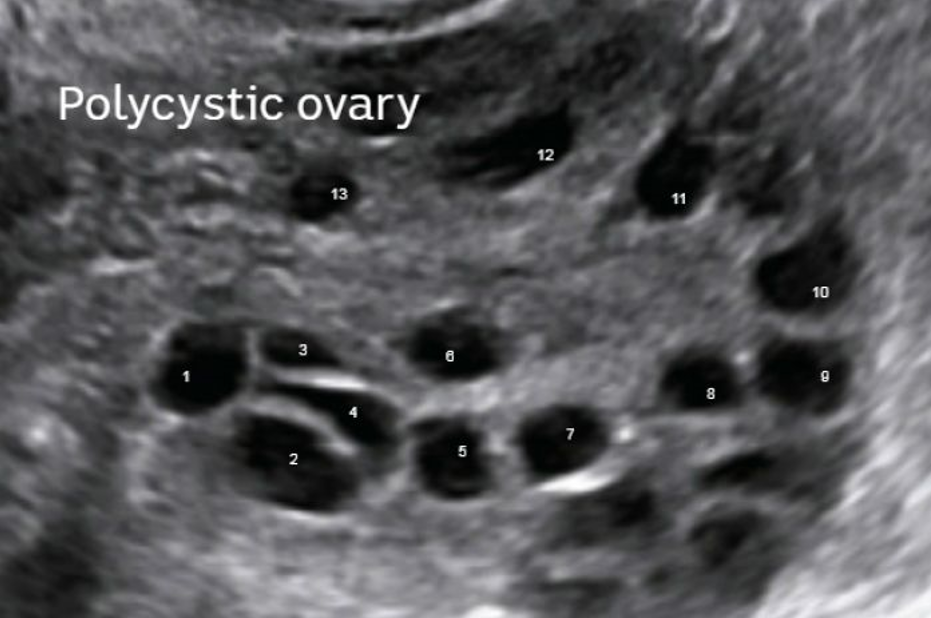

Ky sindrom e ka marrë emrin “vezore policistike” (apo shumë cista), meqë vezoret janë të mbushura përplot me cista të vogla ujore që përmbajnë në vete qeliza të papjekura vezë të cilat nuk arrijnë të zhvillohen deri në atë fazë që gruaja të mund të ngelë shtatzanë. Shkaktari i vërtetë i kësaj patologjie në vezore nuk dihet, por besohet se kryesisht ka të bëjë me gjenetikë dhe me sëmundjen e sheqerit.

– Vezoret e zmadhuara dhe të mbushura me shumë cista të imta, që zakonisht diagnostifikohen lehtë në ultrazë.